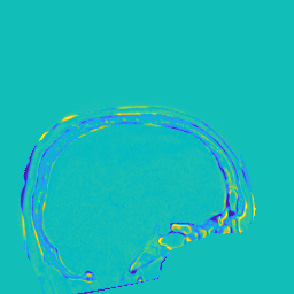

Model-based treatment planning for transcranial ultrasound therapy typically involves mapping the acoustic properties of the skull from an x-ray computed tomography (CT) image of the head. Here, three methods for generating pseudo-CT images from magnetic resonance (MR) images were compared as an alternative to CT. A convolutional neural network (U-Net) was trained on paired MR-CT images to generate pseudo-CT images from either T1-weighted or zero-echo time (ZTE) MR images (denoted tCT and zCT, respectively). A direct mapping from ZTE to pseudo-CT was also implemented (denoted cCT). When comparing the pseudo-CT and ground truth CT images for the test set, the mean absolute error was 133, 83, and 145 Hounsfield units (HU) across the whole head, and 398, 222, and 336 HU within the skull for the tCT, zCT, and cCT images, respectively. Ultrasound simulations were also performed using the generated pseudo-CT images and compared to simulations based on CT. An annular array transducer was used targeting the visual or motor cortex. The mean differences in the simulated focal pressure, focal position, and focal volume were 9.9%, 1.5 mm, and 15.1% for simulations based on the tCT images, 5.7%, 0.6 mm, and 5.7% for the zCT, and 6.7%, 0.9 mm, and 12.1% for the cCT. The improved results for images mapped from ZTE highlight the advantage of using imaging sequences which improve contrast of the skull bone. Overall, these results demonstrate that acoustic simulations based on MR images can give comparable accuracy to those based on CT.